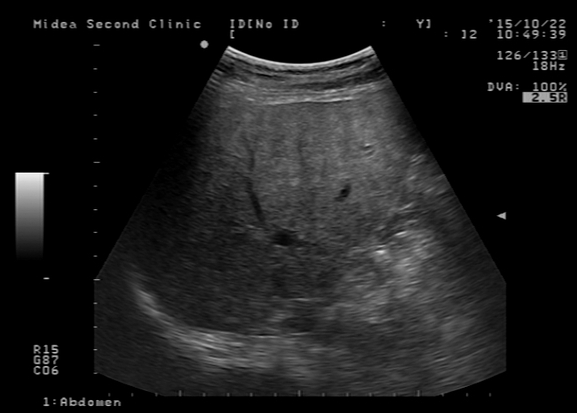

就这样过了一个多月 , 张博发现自己腹痛腹泻的频率越来越高了 , 并且还出现了浑身无力、恶心、呕吐的症状 。 察觉到不对劲的他赶紧来到了医院检查身体 。 经过详细的检查 , 医生发现他的肝脏左叶肿大且有压痛 , 肝脏已经被肝吸虫严重感染 , 已经有肝硬化的表现 。 看着手里的检查报告张博开始慌了 , 他怎么也想不通自己好端端的怎么会患上肝硬化呢?顿时无力地瘫倒在地上 。